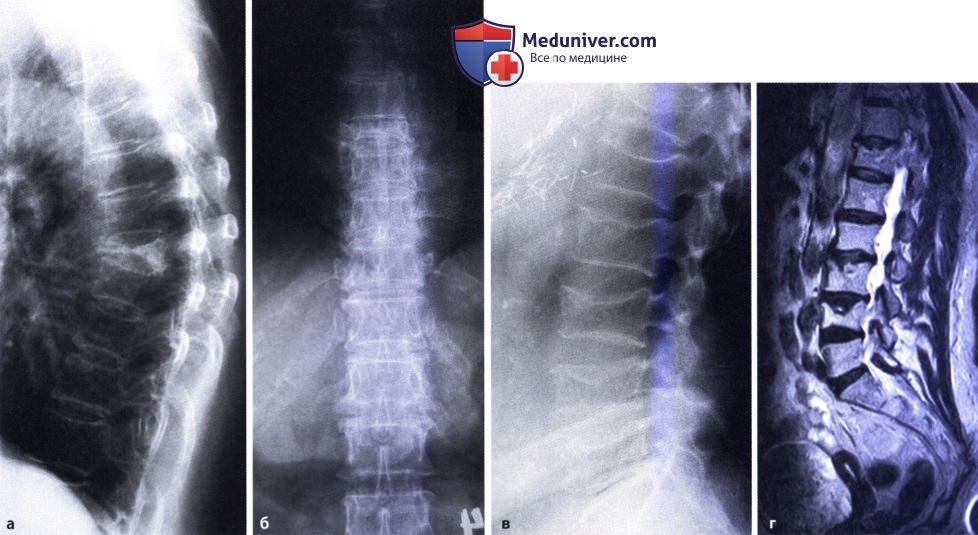

Иллюстрации и снимки, связанные с остеопенией шейки бедра

Раздел: Необычные решения